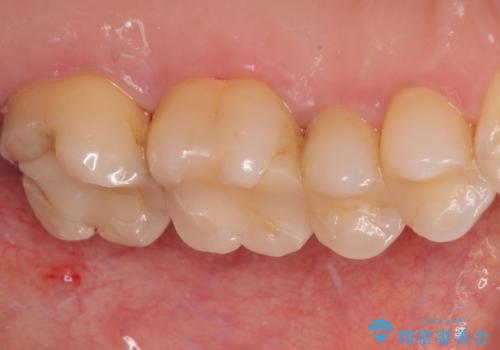

ゴールドインレーは銀歯のインレーやセラミックインレーと比べ、「技工操作の精度が高く、適合が著しく良い」というメリットがあります。特に上の奥歯は歯科医師の操作が行いにくいため、「適合の良さ」は再治療のリスクを防ぐ上でとても重要な要素となります。

上の奥歯は金属色が見えることもないため、審美的な問題は全くありません。

咬み心地はとても良好で、全く違和感がなく、患者様には大変満足していただきました。